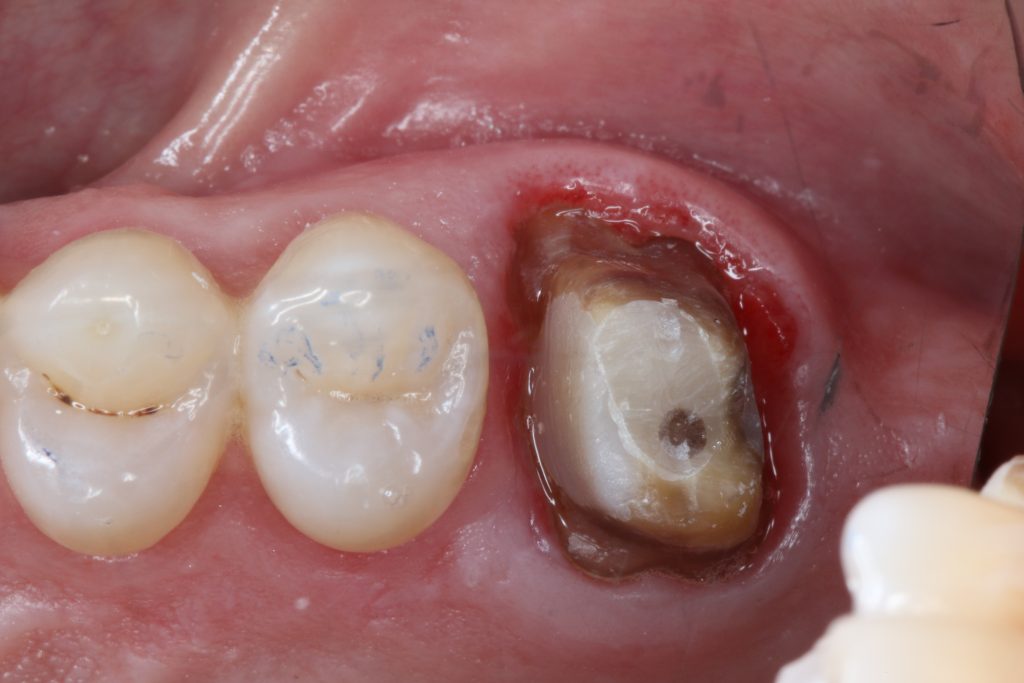

- Opis przypadków klinicznych.

Materiały do odbudowy pośredniej w ciągu ostatnich kilku lat przeszły dość dużą ewolucję, czego rezultatem jest dostarczenie lekarzom praktykom wielu różnorodnych rozwiązań w tej dziedzinie i możliwość ich wykorzystania u pacjentów. Jednakże większy wybór materiałów często szedł w parze z większą liczbą kroków, jakie należało wykonać podczas procesu cementowania, zwłaszcza że zastosowanie danego materiału zazwyczaj wiązało się z zastosowaniem specyficznej dodatkowej procedury, dedykowanej dla danego materiału. Przykładem może być to, że polepszona retencja materiału często [...]